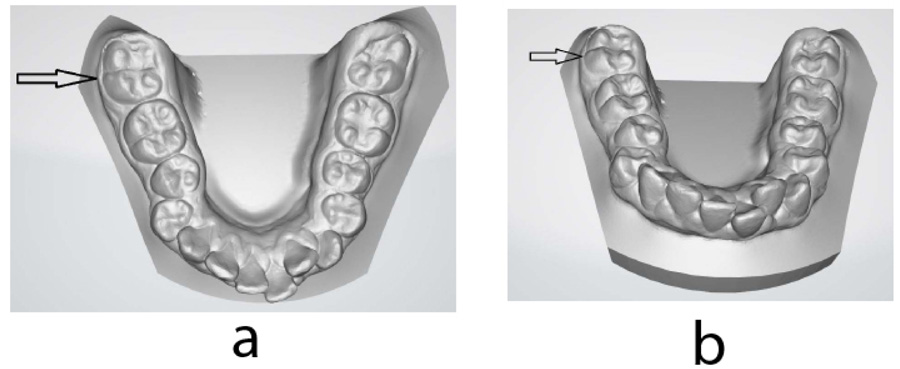

Intraoral models were obtained using a three-dimensional (3D) intraoral scanner (iTero Element, Align Technology, USA). Detailed examination of the intraoral model revealed additional buccal- protostylid-like cusp (Fig. 10). The diagnosis of radix paramolaris (RP) was made based on the findings.

It is further reported that the supernumerary PMM root with an additional root canal is often associated with an increased number of cusps; usually, an additional cusp is observed on the buccal side of the crown (protostylid) [13, 6]. It should be noted, however, that vice versa may not always be the case; an increased number of cusps may not be related to the increased number of PMM roots [6]. In this case, we observed an additional rudimentary buccal, protostylid-like cusp on the PMM with RP only. The use of digital 3D models can provide the clinician with additional tools to allow or to alleviate the identification of morphological signs indicative of possible supernumerary roots. Further development of artificial intelligence might allow automatization of special morphology recognition, indicating the possibility of special morphological features such as supernumerary roots [37].